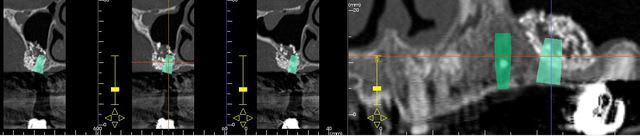

J'ai réalisé un sinus lift, il y a 6 mois et voici le scan de contrôle.

Résultat: Fuite de bio-oss par le volet latéral et surtout un aspect irrégulier du matériau de comblement.

J'ai pourtant utilisé une membrane Copios de chez Zimmer.

Vachement intéressant, pourquoi l'aspect irrégulier? en fait y' a pas eu de re vascularisation dans ta greffe il semble, donc pas d'os formé en 6mois.

Pourtant c 'est bien fait , vu les images .